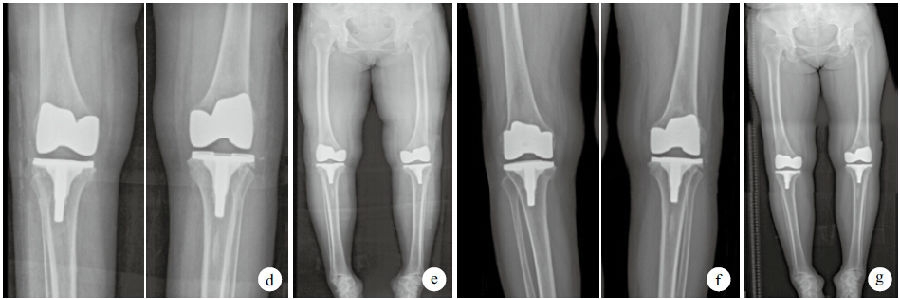

重度膝内翻畸形 完美截骨矫形 内翻38度 - 好大夫在线

a 术前双膝关节正位x线片 b 术前双下肢全长x线片 c 术中缩小胫骨平台

在进行关节手术之前,曲珍患有重度内翻膝,生活已难自理,全靠拐杖支撑